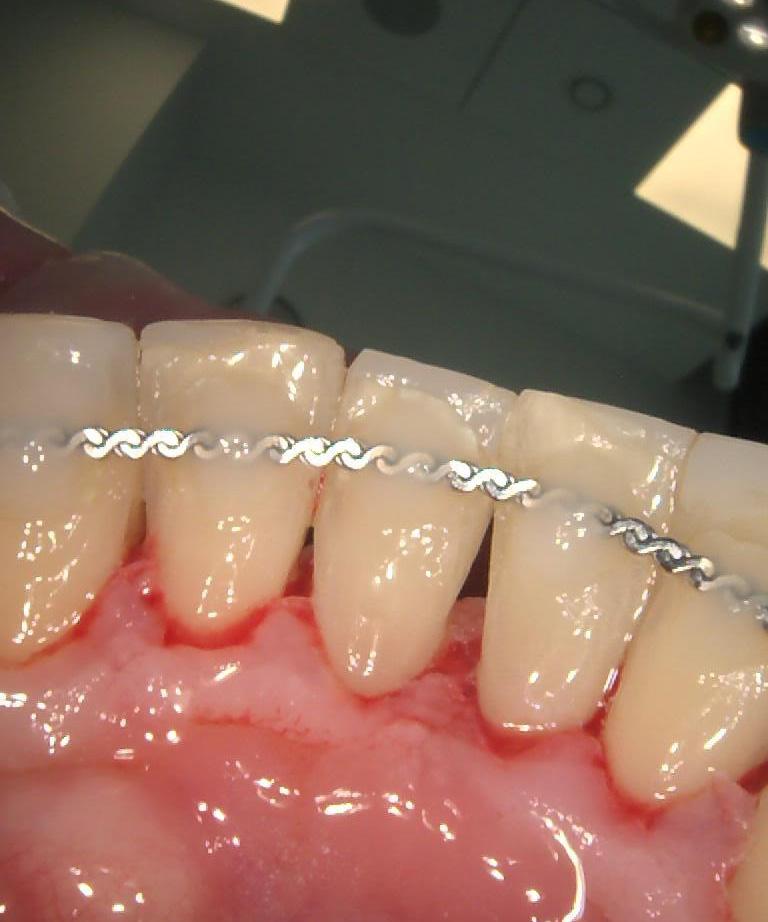

Pacjent po długotrwałym leczeniu chirurgicznym i ortodontycznym w Klinice Platinum został skierowany do lekarza protetyka dr Magdaleny Zawirskiej celem zlikwidowania obecnych trem i diastemy oraz poprawy kształtu zębów.

dr Magdalena zastosowała innowacyjną metodę odbudowy zębów, znaną jako bonding. To bezpieczna i nieinwazyjna technika, która nie wymaga szlifowania zębów. Dzięki wykorzystaniu materiału kompozytowego, został osiągnięty natychmiastowy efekt – od razu już po jednej wizycie.

Teraz Pacjent może pochwalić się pięknym uśmiechem!